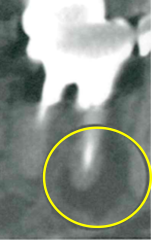

レントゲンでは不明な根尖病巣がCTでははっきり写ります。

同じ患者様です。根管が樋状根になっているのもわかります。